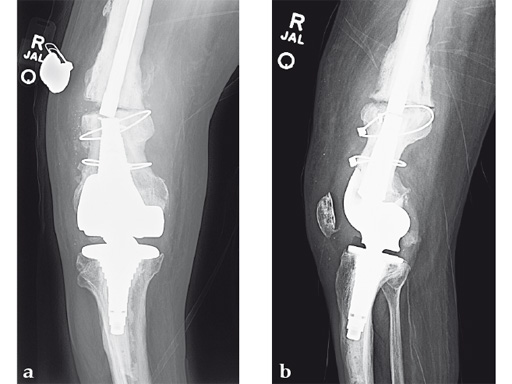

Case 2: A 69-year-old man following revision total knee arthroplasty with a megaprosthesis, requiring an osteotomy of his femoral shaft for realignment of his femoral component. The patient developed a nonunion of his osteotomy and subsequently fractured the stem of his megaprosthesis.

Surgical treatment of this nonunion consisted of compression plating using the VA-LCP Curved Condylar Plate. The arthroplasty components were stable. The proximal piece of the stem was extremely well fixed. Variable-angle locked screws were targeted between his femoral shell and stem in the distal segment allowing excellent distal fixation such that an articulated tensioning device could be attached proximally and the nonunion could be compressed and the alignment improved.